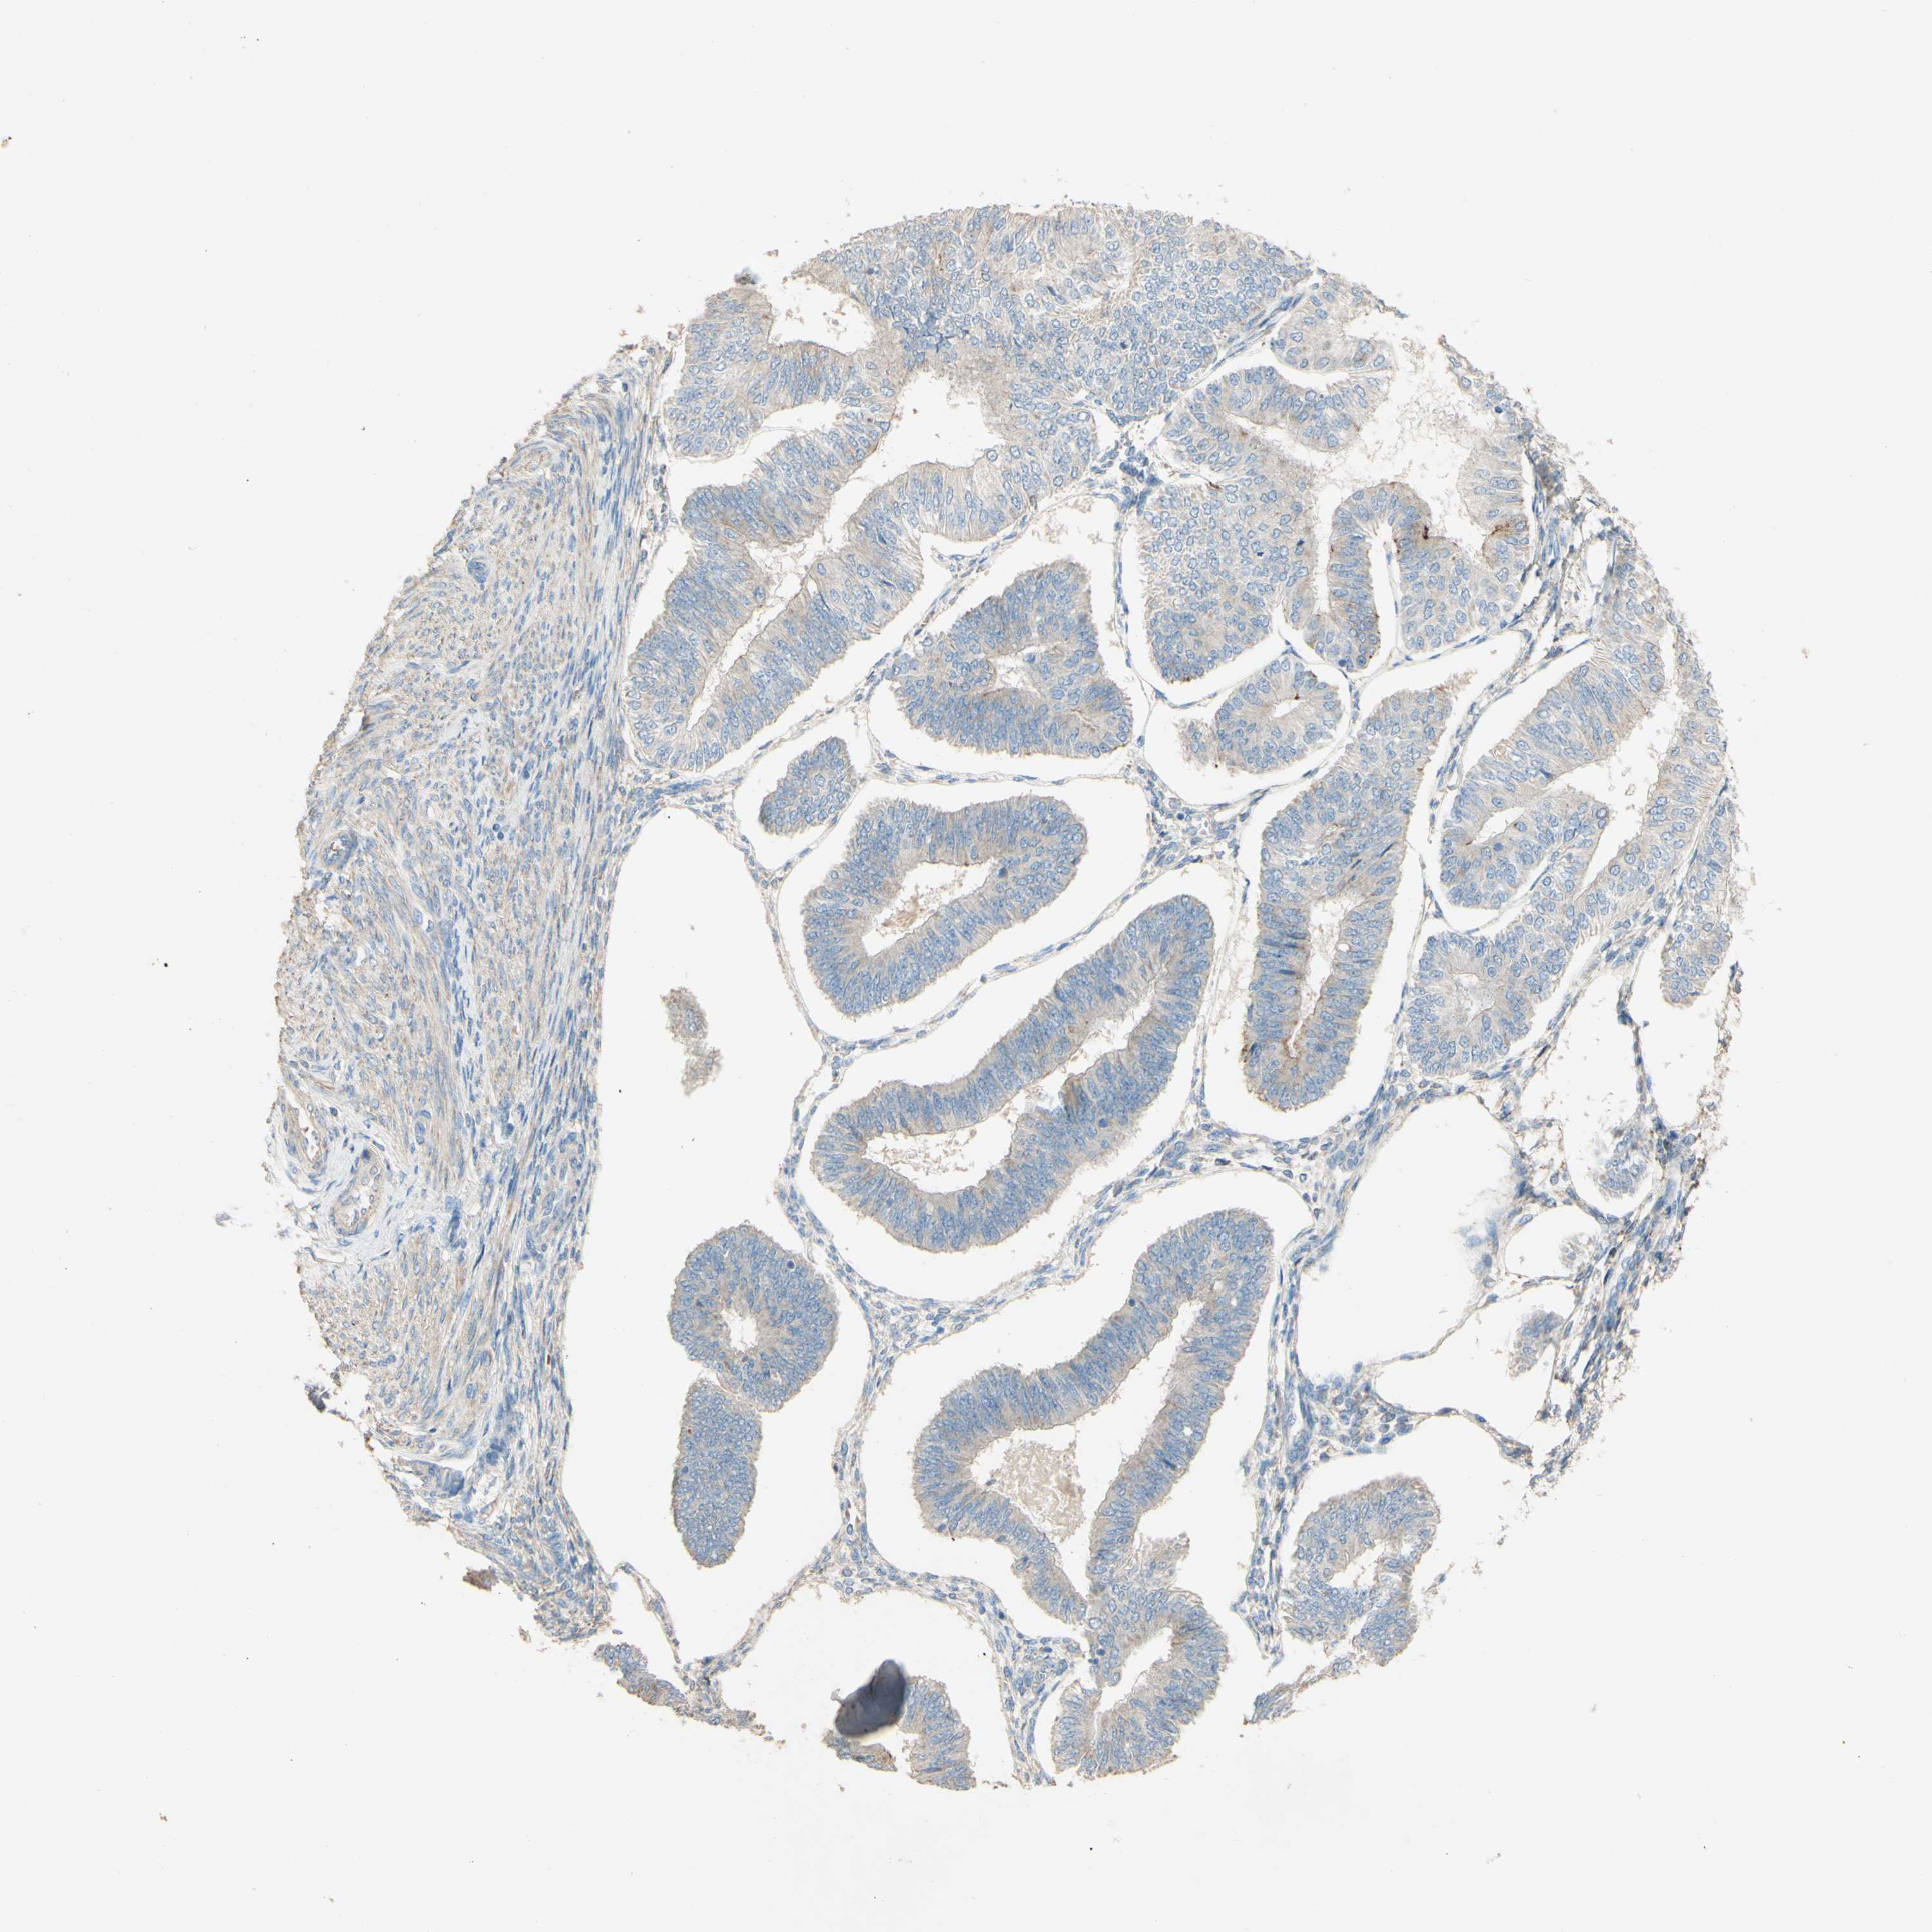

ENDOMETRIAL CANCER - Protein expressioni

A mouse-over function shows sample information and annotation data. Click on an image to view it in a full screen mode. Samples can be filtered based on level of antibody staining by selecting one or several of the following categories: high, medium, low and not detected. The assay and annotation is described here.

Note that samples used for immunohistochemistry by the Human Protein Atlas do not correspond to samples in the TCGA dataset.

Antibody stainingi

Antibody staining in the annotated cell types in the current human tissue is reported as not detected, low, medium, or high, based on conventional immunohistochemistry profiling in selected tissues. This score is based on the combination of the staining intensity and fraction of stained cells.

Each image is clickable and will lead to virtual microscopy that enables deeper exploration of all samples and also displays staining intensity scores, fraction scores and subcellular localization as well as patient and tissue information for each sample.

Antibody HPA011868

Antibody CAB024949

Staining

High

Medium

Low

Not detected

Intensity

Strong

Moderate

Weak

Negative

Quantity

>75%

75%-25%

<25%

None

Location

Nuclear

Cytoplasmic/membranous

Cytoplasmic/membranous,nuclear

Adenocarcinoma, NOS

Adenocarcinoma, metastatic, NOS